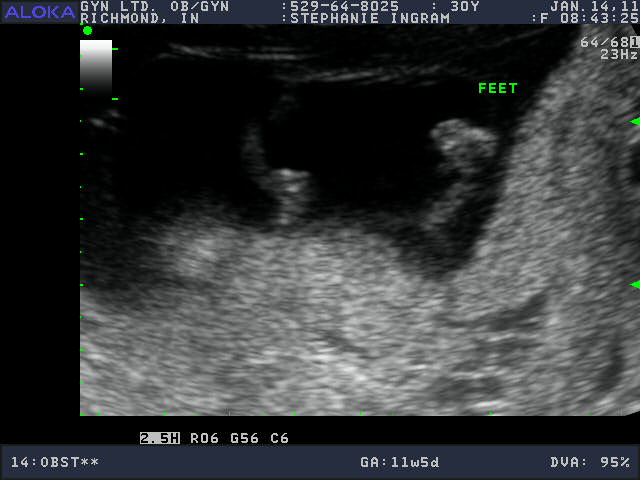

Cute Baby! 12 weeks along